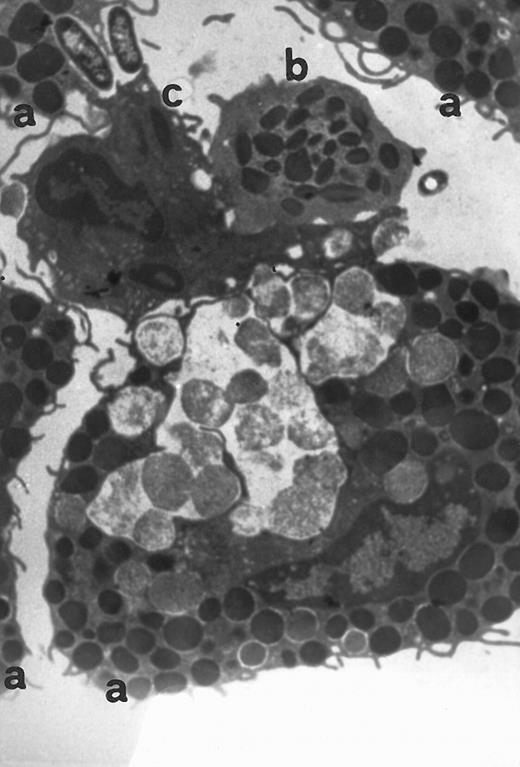

Electron microscopy of skin injection sites.To better analyze the skin injection sites exposed to RANTES, an electron microscopic study was performed. Here we show a representative experiment of four (Fig 4). This electron micrograph (×13,800) depicts accumulation of four basophilic cells (a), one eosinophil (b), and a macrophage (c), 4 hours from injection, with a pattern describing a typical inflammatory event and showing chemoattraction activities toward several cell types.

Transmission electromicrography of a representative experiment of rat inflamed injection site produced by RANTES 10 ng. The section showing the kinetics of the dermal response to exogenous RANTES 4 hours after injection. Evidence for intravascular activation of basophilic cells (a), eosinophil (b), and macrophage (c). Original magnification × 13,800.

In the study presented here, after injection of RANTES and MCP-1 chemokines in the rat, an inflammatory reaction ensued as evidenced by way of histologic characterization of cell extravasation and Evan's blue extravasation. RANTES (10 ng/50 μL) generated a greater response than MCP-1 (10 ng/50 μL). RANTES and MCP-1 activity is evident not only for basophilic cells but also for monocytes and eosinophils (Fig 4). Results show that RANTES and MCP-1 are potent pro-inflammatory proteins and can chemoattract mast cells,30,31 in addition to other inflammatory cells. Data obtained in our in vivo model indicate that RANTES provokes a dose-dependent increase in HDC mRNA synthesis in tissue homogenates biopsed at the injection site. The induction of HDC transcripts occurred within 4 hours. The stimulatory effect of RANTES on HDC mRNA expression was compared with that of LPS (positive control). This effect was abolished in the presence of actinomycin D,17 which inhibits mRNA transcripts. Again the effect of MCP-1 on HDC mRNA generation was less effective than RANTES. To better evaluate the role of RANTES and MCP-1 in basophilic cell activation, we also studied the generation of PGD2 in the skin injection sites and found that RANTES strongly stimulates the release of PGD2 , while MCP-1 is less effective in this bioassay.